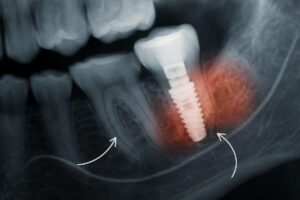

The focus keyword “prosthodontist” represents a dental specialist who uniquely balances these clinical and artistic elements. Prosthodontists approach each procedure with a scientific mindset, employing evidence-based techniques to deliver reliable and long-lasting outcomes. Whether it’s using innovative dental ceramics or cutting-edge implant technology, prosthodontists continually push the boundaries of what’s possible in cosmetic dentistry. Their scientific approach, combined with their artistic flair, allows them to craft smile transformations that are not only visually stunning but also functionally robust. This dedication to scientific excellence is why prosthodontists are trusted to lead the way in advanced cosmetic dental care.